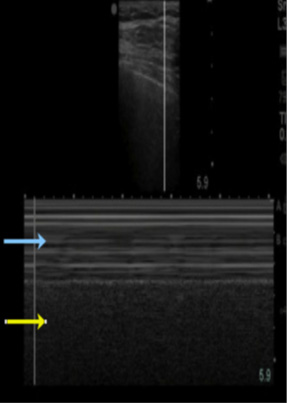

Fluid can collect in the space between the spleen and the left kidney, the splenorenal flexure, similarly to the right side, settling between the 2 organs. Its exploration is similar to that of the right side, except for the higher and posterior location of the left kidney due to the little displacement produced by the spleen, for this reason visualization is more difficult due to the acoustic shadows produced by the ribs and requires that the evaluation be performed during the patient's inspiration, without forgetting that the transducer must be in a more posterior position (Figure 5 A and B). A complete evaluation should include the space between the spleen and the left kidney in its entirety to look for free fluid. Contrary to the evaluation of the right side, it is very common for the fluid to be located between the spleen and the diaphragm, so this area should also be examined.

Splenic renal fossa; examination with a low-frequency transducer with a cephalad marker: it allows us to observe: splenic renal fossa and infradiaphragmatic space.

Figure 5A.                                           Figure 5B.

Figure 5A Free renal splenic space (light blue arrow: left kidney, yellow

arrow spleen; 5B. Anechoic image in (yellow arrow) corresponding to intraabdominal

free fluid.